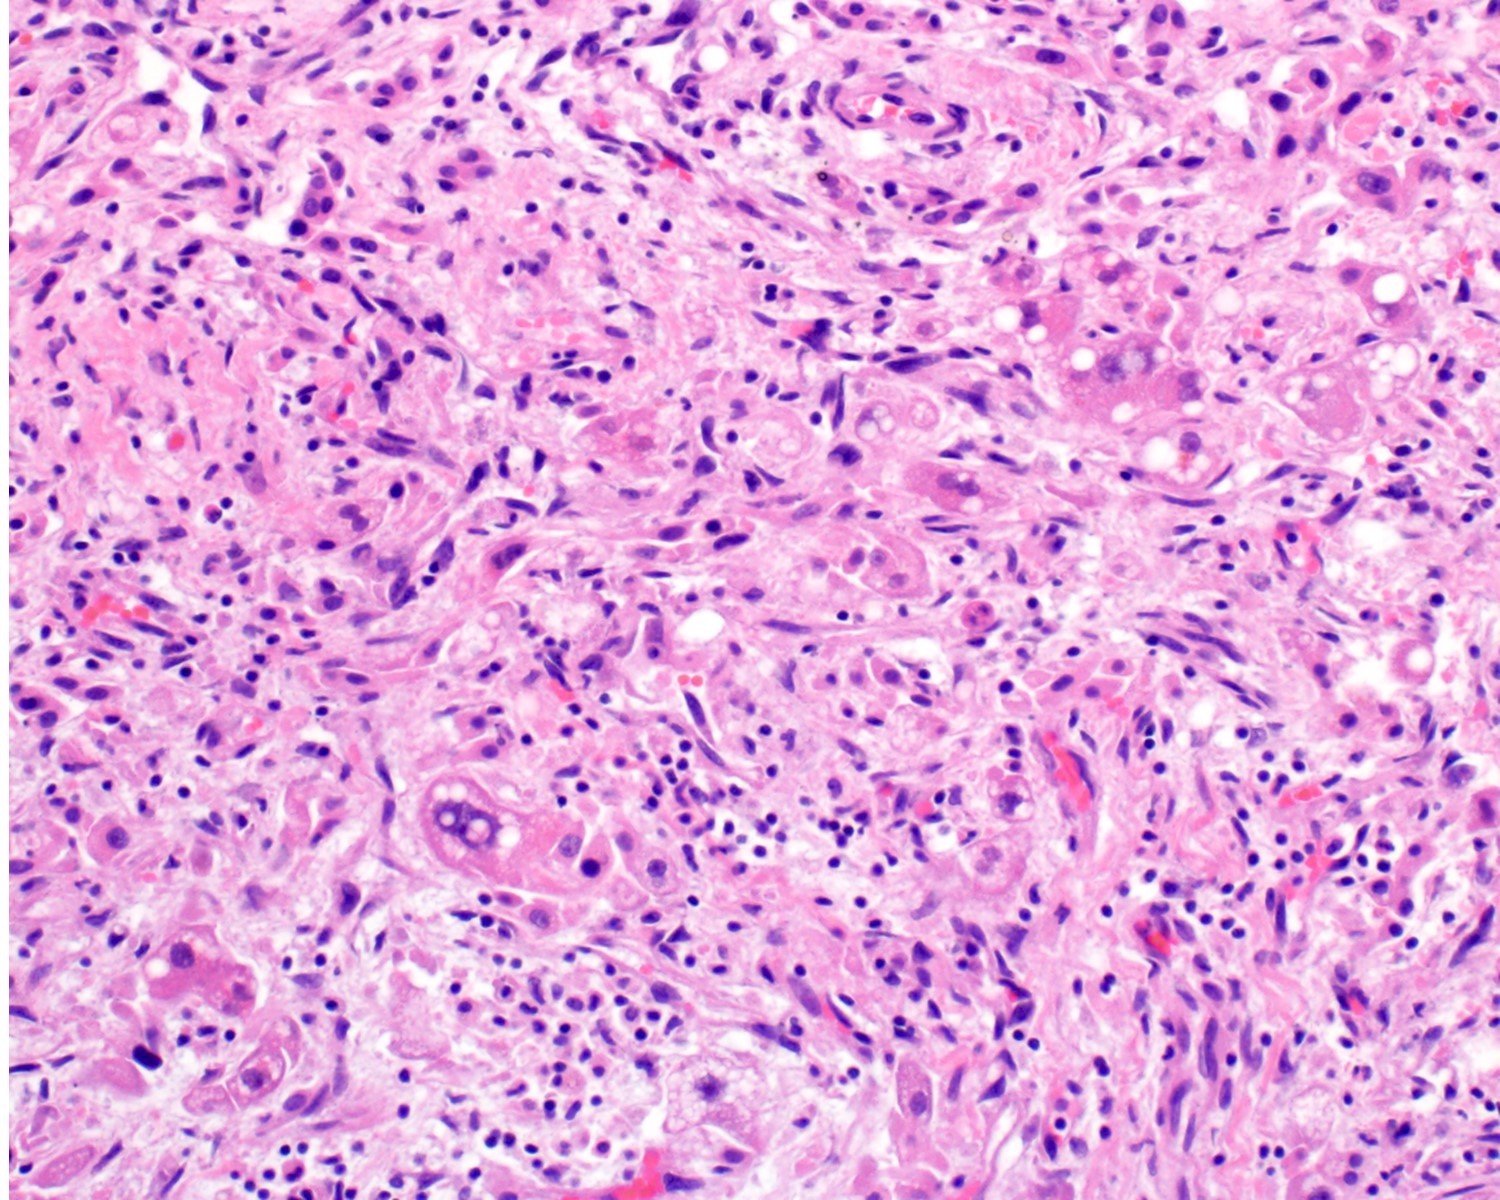

- 2 main histologic growth patterns were described (Am J Surg Pathol 2019;43:581)

- Mass forming

- Vasoformative shows architectural complexity and interconnecting vascular channels

- Anastomosing vessels and haphazard vascular channels

- Endothelial cells show tufting, atypia and mitotic figures

- Nonvasoformative shows epithelioid to spindled morphology

- Epithelioid morphology (epithelioid angiosarcoma) is most common (Am J Surg Pathol 2004;28:298)

- Solid nests or sheets of tumor cells

- Tumor often invades into sinusoids and hepatic venules at the periphery

- Cells have eosinophilic cytoplasm and oval nuclei

- Chromatin can be vesicular

- Multinucleated giant cells can be present

Microscopic (histologic) images

A 55 year old man presents with abdominal pain, weight loss and hepatomegaly. Laboratory studies reveal elevated liver enzymes but normal alpha fetoprotein levels. A liver core needle biopsy is performed. ERG immunohistochemistry is shown in the second image above. What is the most likely diagnosis?

E. Liver angiosarcoma. The histopathology shows nests and sheets of highly atypical neoplastic cells with hyperchromatic and pleomorphic nuclei, which are highlighted by ERG immunohistochemistry in the second image above. This makes liver angiosarcoma the most likely diagnosis.